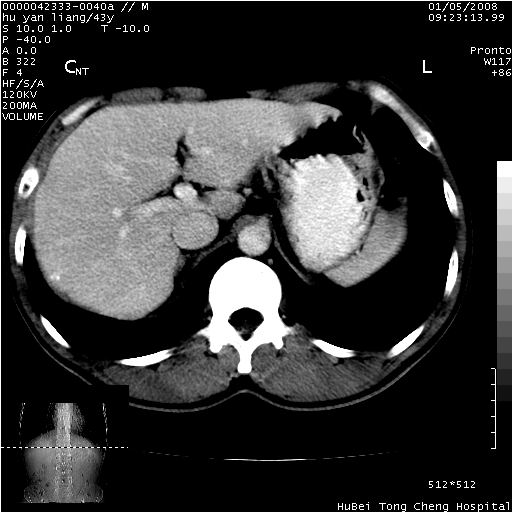

患者 男,43岁。右上腹不适1年余。既往有“肝右叶肝脓肿”病史,经保守治疗后痊愈。

b超提示:1)肝右叶肝内胆管结石。2)肝右叶占位性病变待排。

上中腹部ct轴位平扫+增强扫描(层厚10mm,螺距1.0,重建间隔10mm),图像如下:

肝右上叶偏后方较大团片状钙化灶,支持:肝脓肿后遗改变!

肝右叶后段团块状钙化灶,结合病史考虑肝脓肿痊愈后表现。